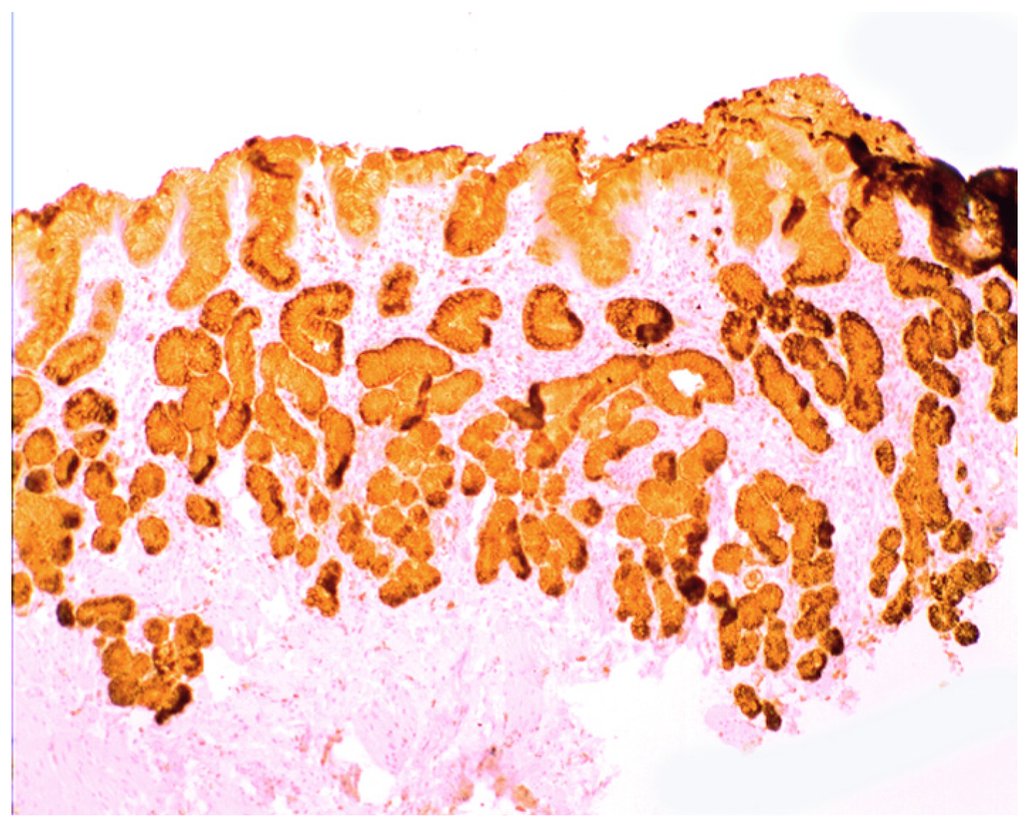

In collagenous colitis lysozyme is up-regulated in the colonic crypts and in metaplastic Paneth cells [9] (Figure 11). In lymphocytic colitis, lysozyme is up-regulated in macrophages underlying the surface epithelium of the lamina propria [9] (Figure 12), as well as in the lower part of the crypts (Figure 13).

Collagenous colitis. Marked lysozyme immunoreactivity in goblet cells in the crypts (lysozyme immunostain, ×40).